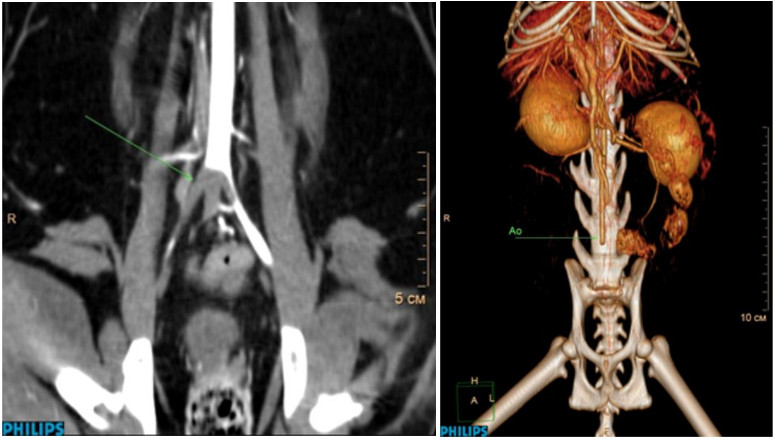

КТ-ангиография – наглядный метод диагностики, который может быть использован для демонстрации расположения тромба. По КТ-ангиографии оценивают дефект заполнения артериального сосуда контрастным веществом (рис. 7).

Помимо расположения самого тромба на КТ, необходимо исследовать другие ткани и органы на наличие дефектов контрастирования. В нашей практике у животных с ТЭК мы обнаруживали мелкие инфаркты коркового слоя почек, которые до этого не удавалось выявить на УЗИ (рис. 8), и сегментарный дефект распределения контраста в паренхиме селезенки.